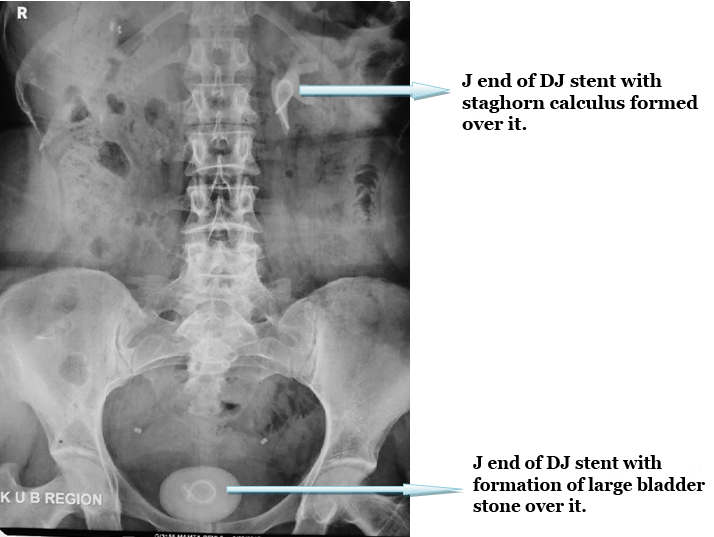

Ultrasound kidney, ureter, and bladder of the patient revealed essentially right sided normal kidney, while in left kidney there was a staghorn calculus of size about 25 mm, besides it there was a large bladder stone of size about 49 mm. Digital X-ray kidney, ureter, and bladder showed coiled ends of a double-J stent in the left renal pelvis and bladder region with formation of stones over it however entire shaft of the stent was missing (Figure 1). Her KFT was within the normal limit.

Figure 1: Digital X-ray kidney, ureter, and bladder of the patient showing A large bladder stone and a large staghorn calculus (in left renal pelvis) formed over J ends of double-J stent while central shaft has been disappeared due to stenturia.

Figure 3: Digital X-ray kidney, ureter, and bladder of patient showing complete clearance of stone with DJ stent insitu.